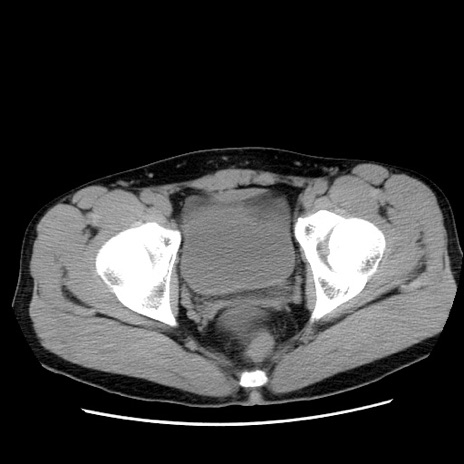

冠状断像

【症例】20歳代 男性

【主訴】心窩部痛

【現病歴】今朝より上腹部痛あり。一旦軽快していたが再度出現したため救急要請。昨日夕に白身の魚を含む刺身を食べた。

【身体所見】BP 136/89mmHg、HR 74/min、BT 37.0℃、腹部:膨満、軟、心窩部に圧痛あり。反跳痛なし、筋性防御なし、腸雑音やや亢進あり。

【データ】WBC 17700、CRP 0.48